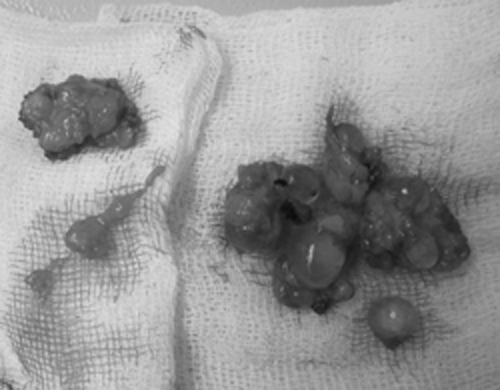

Các khối silicon bị vón cục lấy ra từ ngực bệnh nhân. Ảnh: Thiên Chương

Bác sĩ Nguyễn Văn Việt Hảo, Giám đốc trung tâm thẩm mỹ Hàn Quốc, cho biết silicon lỏng đã gây biến chứng. Thay vì tụ thành khối, các mảng silicon đã tách rời ra.

"Để ngực bệnh nhân không bị xâm lấn, chúng tôi đã phẫu thuật loại bỏ silicon. Rất nhiều vón cục silicon dạng quả trứng được lấy ra. Tuy nhiên, việc nạo vét silicon vẫn không thể trọn vẹn vì có thê ảnh hưởng đến mô ngực", ông Hảo cho hay.